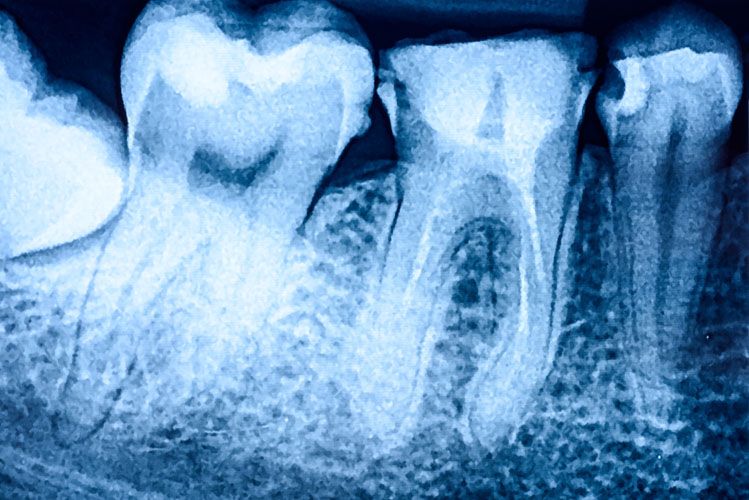

CT Scans Improve Dental Implant Surgery

Advancements in dental technologies have allowed dentists to improve the delivery of Dental Implants to their patients.  The use of dental CT scans have allowed more accurate, and safe placement of dental implants, while minimizing the surgical time. For decades, the CT scan has been used in medicine to evaluate the condition of bony structures throughout the body.  Much like an MRI, it captures a 3-Dimensional view of the desired area.  The major difference is that the CT scan is an x-ray exam.  It is meant to diagnose the health, quality, and...